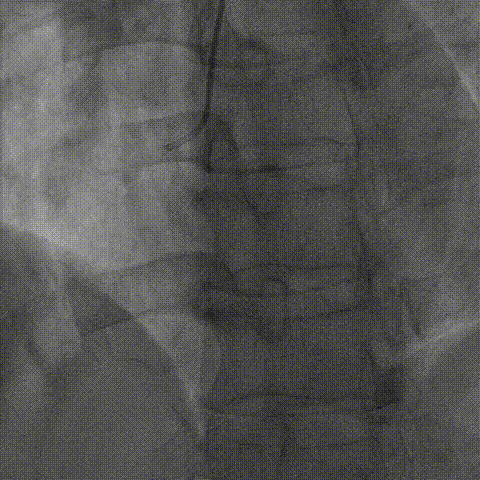

逆向器械:

1、选择近段粗大间隔支;Finecross(150cm);Sion导丝surfing通过侧枝循环至右冠远段,跟进微导管后尝试UB3、Gaia3导丝至闭塞段远段与正向导丝重叠,但闭塞段钙化可能导丝逆向导丝无法进一步前进突破。